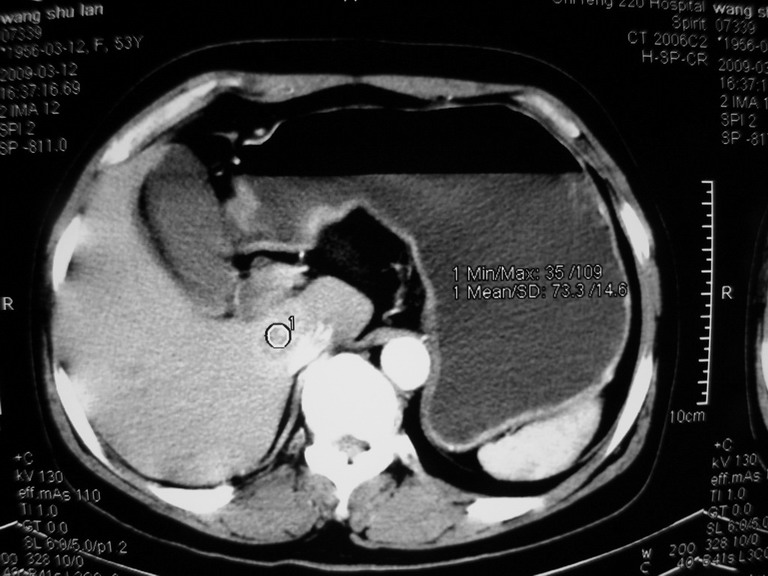

患者,女性50岁,上腹部不适2年余,既往多次腹部彩超未见异常,今日上午在我院查彩超发现肝右叶囊实性病变,外院辅助检查,afp,cea,ca199, 都在正常范围内,无肝炎史否认肿瘤史,生活在牧区

考虑肝癌。缺少延迟片。

考虑肝右叶与尾叶交界区肝癌(部分外生),侵犯下腔静脉并下腔静脉瘤栓形成。

肝包虫病可能性大